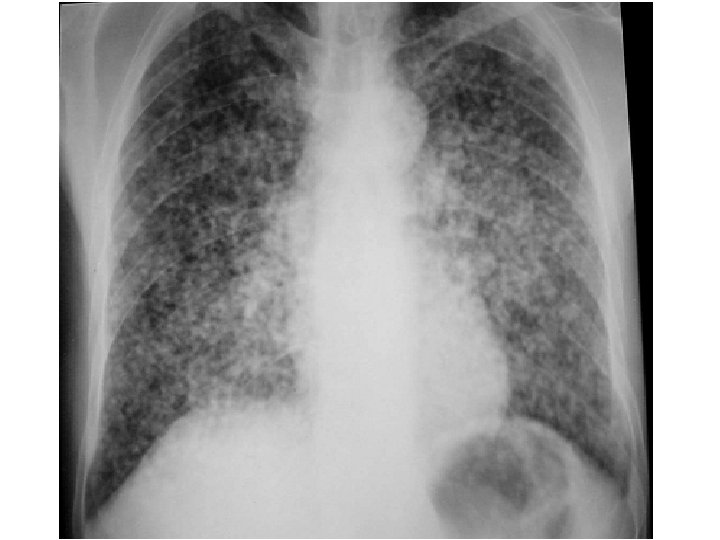

b- Miliaire atypique : • caractérisée par : – Inégalité des tailles. – Irrégularité des contours. – Répartition inhomogène. • N. B : l’association avec d’autres images parenchymateuses, pleurales, médiastinales sera d’une grande utilité pour le diagnostic étiologique.

A- Miliaires infectieuses : 1 - Miliaire tuberculeuse : • • a) Forme généralisée : réalise une miliaire fébrile radiologiquement diffuse (miliaire dans sa forme typique). b) Forme localisée : réalise une miliaire localisée (dans sa forme atypique) avec généralement présence d’une caverne ou d’une ADP fistulisée. 2 - Miliaires bactériennes : • Se son des miliaires fébriles radiologiquement localisés, permet les germe en cause : staphylocoque, pneumocoque, mélitococcie. 3 - Miliaires virales : • Généralement rapidement régressives se rencontrent surtout dans : la grippe, rougeole, MNI. 4 - Miliaires mycosiques : • Généralement calcifiées exemple : la miliaire d’histoplasmose. 5 - Miliaire des parasitoses : exemple : syndrome de Loeffler.